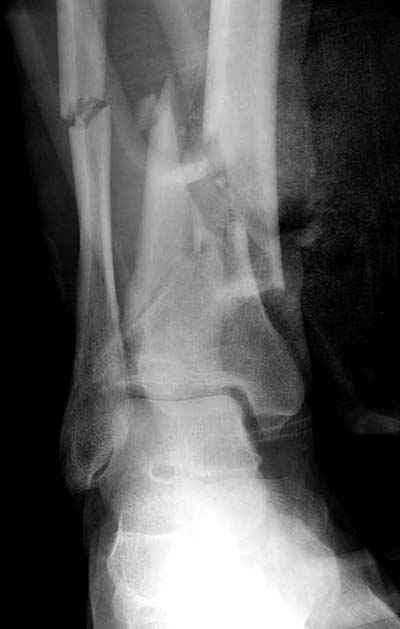

Разбор тактики лечения низких переломов костей голени становится популярной темой. Споры не только по тактике "по данным некоторых зарубежных авторов, при переломе обеих костей голени на одном уровне рекомендуется фиксация обеих", а также по импланту (гвоздь или пластина) и по локализациям имплантов "укладывать на заднюю поверхность при низких переломах"

Во всех описанных случаях единственное, что объединяет, это локализация перелома, а так это различные по механизму травмы. Различные импланты, и хирургическая техника отличается друг от друга. Разные по возрасту и по активности больные. Поэтому из-за невозможности создать единый алгоритм "до сих пор идет дискуссия".

Возвращаясь к разбору "БИОС у пожилого пациента", тогда многие из наших коллег проголосовали за то, чтобы оставить на одном интрамедуллярном гвозде. На рентгене плохое качество кости (остеопороз), костные фрагменты в середине канала, и на малоберцовой имеются фрагменты по линии перелома. В таких случаях гвоздь идеальный фиксатор, потому что создается равномерная компрессия на обе кости. А латеральная фиксация на малоберцовой, как распорка, повела бы в варус.

Здесь представлены несколько примеров снимков с осложнением, медиальная пластина, медиальная в комбинации с латеральной, метод Илизарова, а также сравнительные данные толщины медиальных пластин Synthes 4.4 mm, DePuy 3.2 mm.